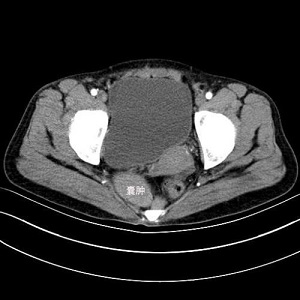

骶前囊肿

骶前囊肿是一类位于盆腔腹膜返折以下,骶骨前间隙的囊肿肿物。常见类型包括表皮样囊肿、皮样囊肿、成熟畸胎瘤等,其中成熟畸胎瘤内含皮肤、肌肉、骨、软骨、消化道上皮、脑等组织。

骶前囊肿发病隐匿,早期常无明显症状,体积较大时,则会压迫周围组织及脏器,囊肿与直肠、阴道、盆壁组织及骶尾骨韧带筋膜关系密切。